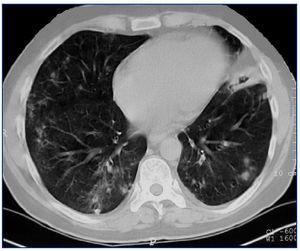

Presentamos el caso de un hombre de 42 años, diagnosticado de GW en el año 2004 mediante biopsia renal. Se inició tratamiento de inducción con bolos de 6-metilprednisolona (500 mg) i.v. durante tres días consecutivos seguida de prednisona oral (1 mg/kg/día) y ciclofosfamida oral a dosis de 100 mg/día (1,5 mg/kg/día). Después de tres meses de tratamiento, el paciente alcanzó la remisión clínica, con negativización de los ANCA-PR3. Durante la fase de mantenimiento, se sustituyó ciclofosfamida por micofenolato mofetil (720 mg/12 h). En 2007, el paciente sufrió una recaída de su enfermedad. Se reinició el tratamiento con ciclofosfamida en bolos intravenosos a dosis de 850 mg (10 mg/kg), junto con prednisona oral (1 mg/kg/día). Las manifestaciones clínicas remitieron y los ANCA-PR3 se negativizaron tras dos meses de tratamiento, pero en enero de 2008 el paciente ingresó por una segunda recaída con hemoptisis e insuficiencia renal. Se administró 1 g de ciclofosfamida intravenosa cada tres semanas junto con prednisona oral (1 mg/kg/día). El paciente continuaba con clínica respiratoria y renal a pesar de haber recibido una dosis acomulada de ciclofosfamida de 16 g y altas dosis de corticoides, por lo que fue diagnosticado de GW refractaria. Se realizó una segunda biopsia renal, que mostró la persistencia de glomerulonefritis necrosante pauci-inmune con reacción extracapilar en el 7% de los glomérulos, fibrosis intersticial-atrofia tubular moderada y glomeruloesclerosis en el 50% del total de glomérulos. Dada la clínica respiratoria de hemoptisis (Figura 1), se iniciaron recambios plasmáticos a días alternos durante 15 días y prednisona oral a dosis de 1 mg/kg/día. Tras finalizar los recambios plasmáticos, se administró rituximab (375 mg/m2 a la semana), durante cuatro semanas. Se monitorizó el tratamiento con rituximab determinando linfocitos B en sangre periférica a través de CD19, niveles de inmunoglobulinas y título de ANCA-PR3 (Tabla 1). Los síntomas respiratorios mejoraron y la función renal se estabilizó (creatinina de 3,6 mg/dl). Todos los marcadores de inflamación disminuyeron, los ANCA-PR3 se negativizaron y no se detectaron linfocitos B en sangre periférica. Como tratamiento de mantenimiento se inició micofenolato mofetil junto con dosis bajas de prednisona. En noviembre de 2008 fue ingresado nuevamente por rectorragia anemizante e insuficiencia renal crónica progresiva sin signos de actividad de vasculitis (ANCA-PR3 negativos); fue diagnosticado de adenocarcinoma de recto y requirió el inicio de la hemodiálisis.

Figura 1. Tomografía computarizada torácica en la que se aprecia una hemorragia pulmonar.